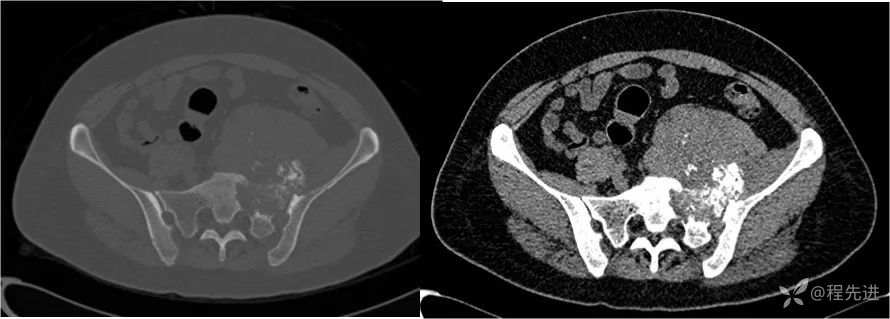

CT

- 是软组织肿瘤累及骨质还是骨肿瘤伴软组织肿块?

- 是软骨基质钙化,还是肿瘤骨?抑或钙化?

- 肿瘤的定性诊断?